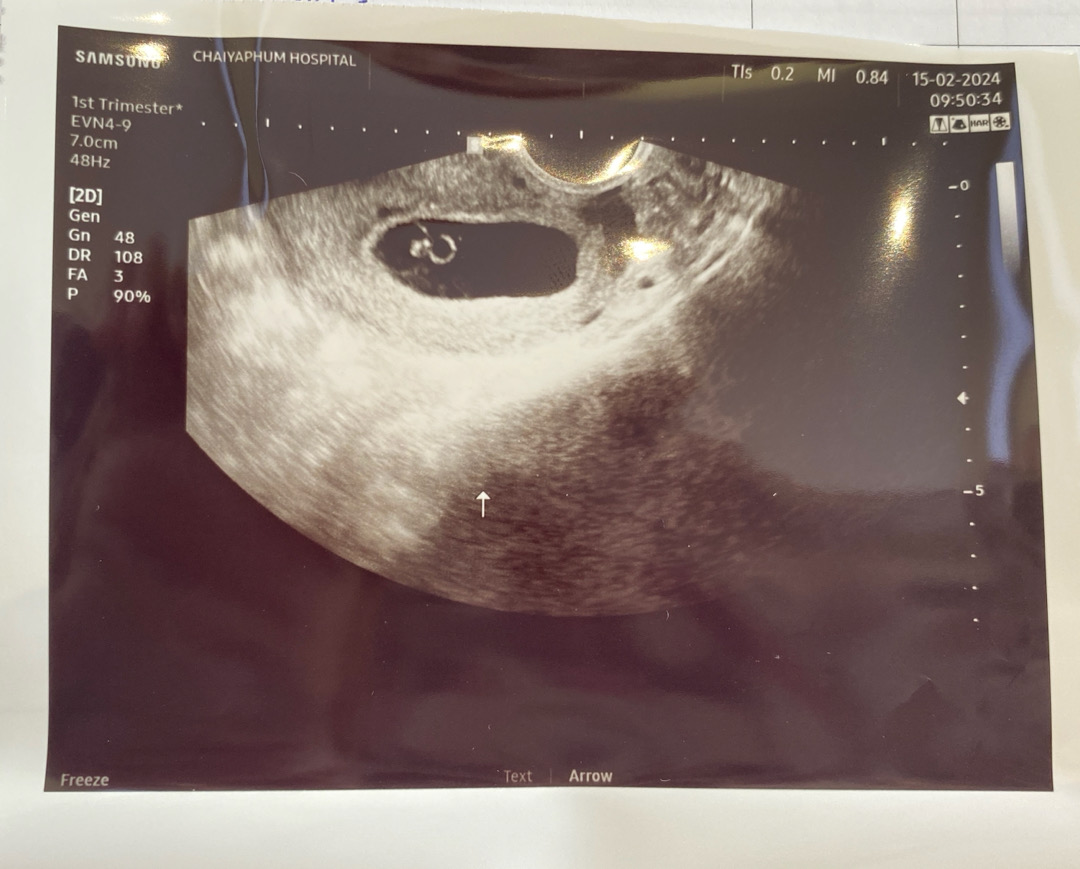

9 WEEKS

จากที่พบหมอตามนัด น้องเจริญเติบโตได้แค่นิดเดียว หมอให้โอกาสอีก1 อาทิตย์นัดอีกครั้ง ถ้ายังไม่เจริญเติบโตมากไปกว่านี้ ต้องยุติการตั้งครรภ์นะ หมอให้ทำใจร้องไห้หนักมากค่ะแม่ๆ☹️☹️